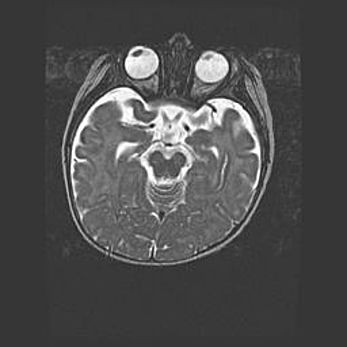

Мальформация Денди-Уокера. Киста задней черепной ямки.

Агенезия мозолистого тела.

Возраст: 2,5 месяца

Вес: 2420 г

Пол: женский

Окружность головы: 37 см

Срок гестации: 32 недели

Мальформация Денди—Уокера — редкий вид патологии ЦНС, представляющий собой врожденный порок развития каудального отдела ствола и червя мозжечка, ведущий к неполному раскрытию срединной (Мажанди) и латеральных (Лушка) апертур IV желудочка мозга. Для этогно синдрома характерна триада симптомов: гипотрофия червя мозжечка и/или полушарий мозжечка, кисты задней черепной ямки, гидроцефалия различной степени. В 70% случаев порок сочетается и с другими аномалиями головного мозга, в частности с агенезией мозолистого тела.